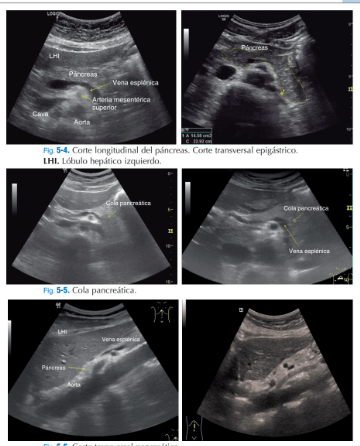

"ECOmécum, la herramienta fundamental para saber deecografía clínica." Con la llegada de los ecógrafos a los servicios de urgencia y atención primaria,resulta imprescindible formarseen su utilización yECOmécumserá la forma de conseguirlo. Orientado para la resolución de cualquier situación comprometida o duda en el diagnóstico ecográfico, este práctico manual, aporta lainformación necesaria en la clínica diaria; centrado especialmente en laecografía abdominal. Con un método sencillo y muy práctico, empieza por la base más fundamental y por unesquema de exploracióncon los cortes necesarios, posición del transductor, elresultado de la imagen ecográfica y la interpretación de la patologíahallada. Sin duda, una fórmula muy efectiva y rápida para el profesional, ya sea joven con poca experiencia o experto con necesidades de actualización en las nuevas técnicas.